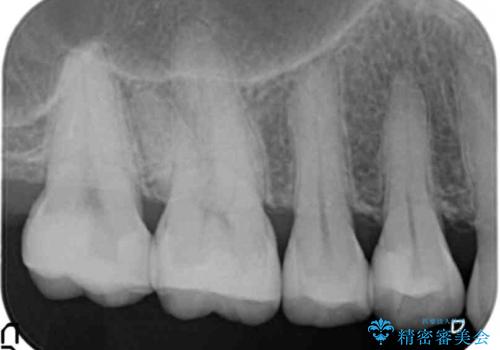

銀歯を白く 虫歯治療

- 虫歯治療を希望して来院。

保険適用の銀色のつめもののやり替えを行いました。

自由診療のインレーの歯型には、シリコンを使用しています。また、処置時には8倍の拡大鏡を用いて、精密に治療しております。